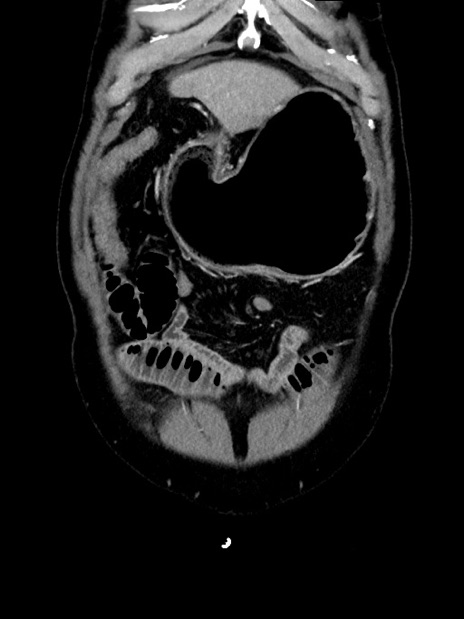

症例35(冠状断像)

【症例】70歳代 男性

【主訴】腹部膨満、嘔吐

【現病歴】昨日より腹部膨満感出現。本日増悪し、仙痛出現。嘔吐あり、受診。

【既往歴】糖尿病、胆摘後

【身体所見】BP 149/80mmHg、HR 74/min、BT 35.9℃、腹部:膨満、軟、圧痛なし。腸雑音減弱あり。上腹部正中切開瘢痕あり。

【データ】WBC 13500、CRP 1.72